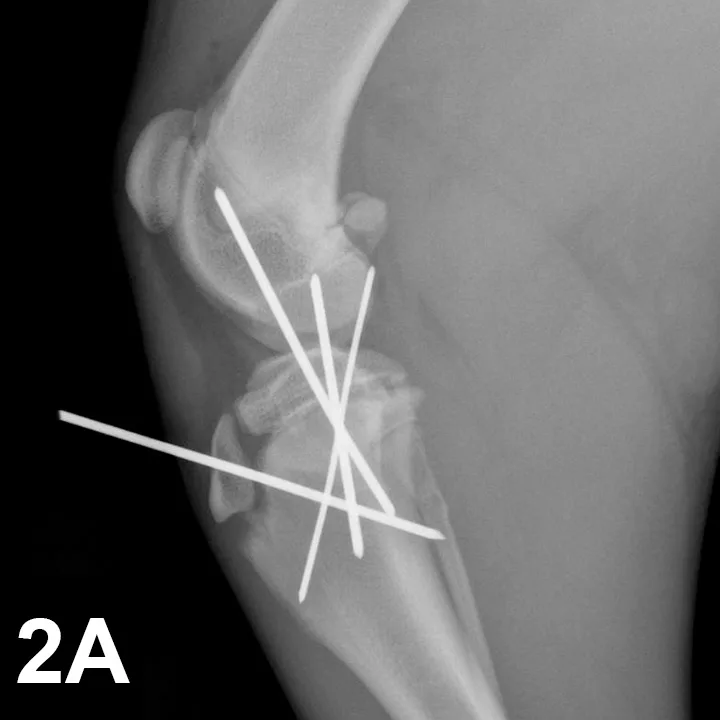

Outcome: Surgery is indicated, and the day following initial presentation, fracture ends were reduced and fluoroscopic-assisted percutaneous pinning of the fractures performed (Figures 2A and 2B, taken before pin ends were trimmed). A lateral splint was placed, and the bandage was changed weekly. Radiographs showed complete healing 4 weeks postoperatively, and the pins were then removed.

The patient’s lameness was grade 2/4 at pin removal; the patella was stable, and no joint instability was detected. A gradual return to physical activity was recommended.